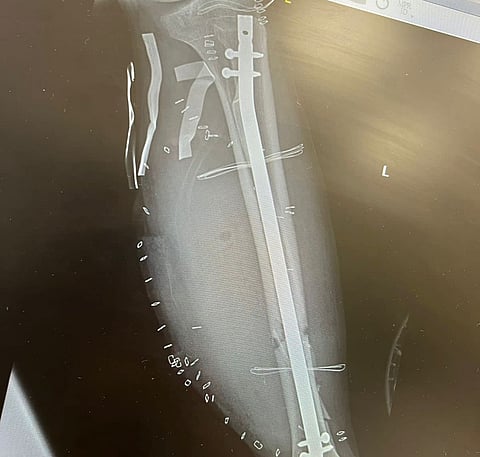

نجح فريق طبي بمجمع الملك فيصل بالطائف في تجميل شاب أصيب في حادث مروري مروع، تسبب له بكسر مركّب من الدرجة الثالثة في عظمتي الساق الأيسر، وانكشاف لمعظم عظمتي الساق.

وقالت "صحة الطائف" في تصريحٍ خاص لـ"سبق": "بعد الفحوصات اللازمة تم إجراء عملية تثبيت داخلي وتغطية للعظام بواسطة أطباء الجراحة بقسم العظام، بعدها تم اتخاذ قرار من قبل فريق جراحة التجميل بقيادة رئيس القسم الدكتور شاكر الفاران".

وأشار إلى أنه أُجريت للمريض عملية جراحية ميكروسكوبية لنقل سديلة عضلية حرة من ظهر المريض إلى ساقه مع توصيل للأوعية الدموية لتغطية الجزء المتهالك من الأنسجة والجزء المكشوف من عظم الساق في عملية استغرقت قرابة العشرين ساعة.